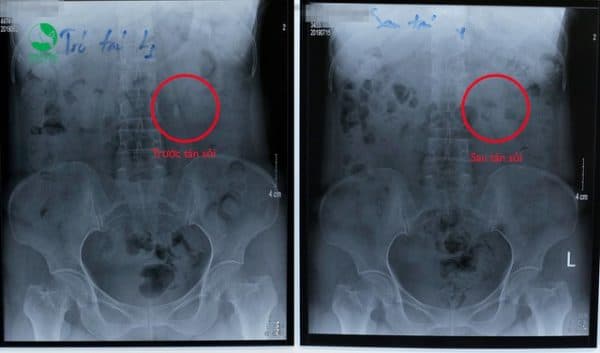

- Hình ảnh so sánh trước – sau của một ca tán sỏi thận ngoài cơ thể. Sỏi đã sạch hoàn toàn sau 1 lần tán.